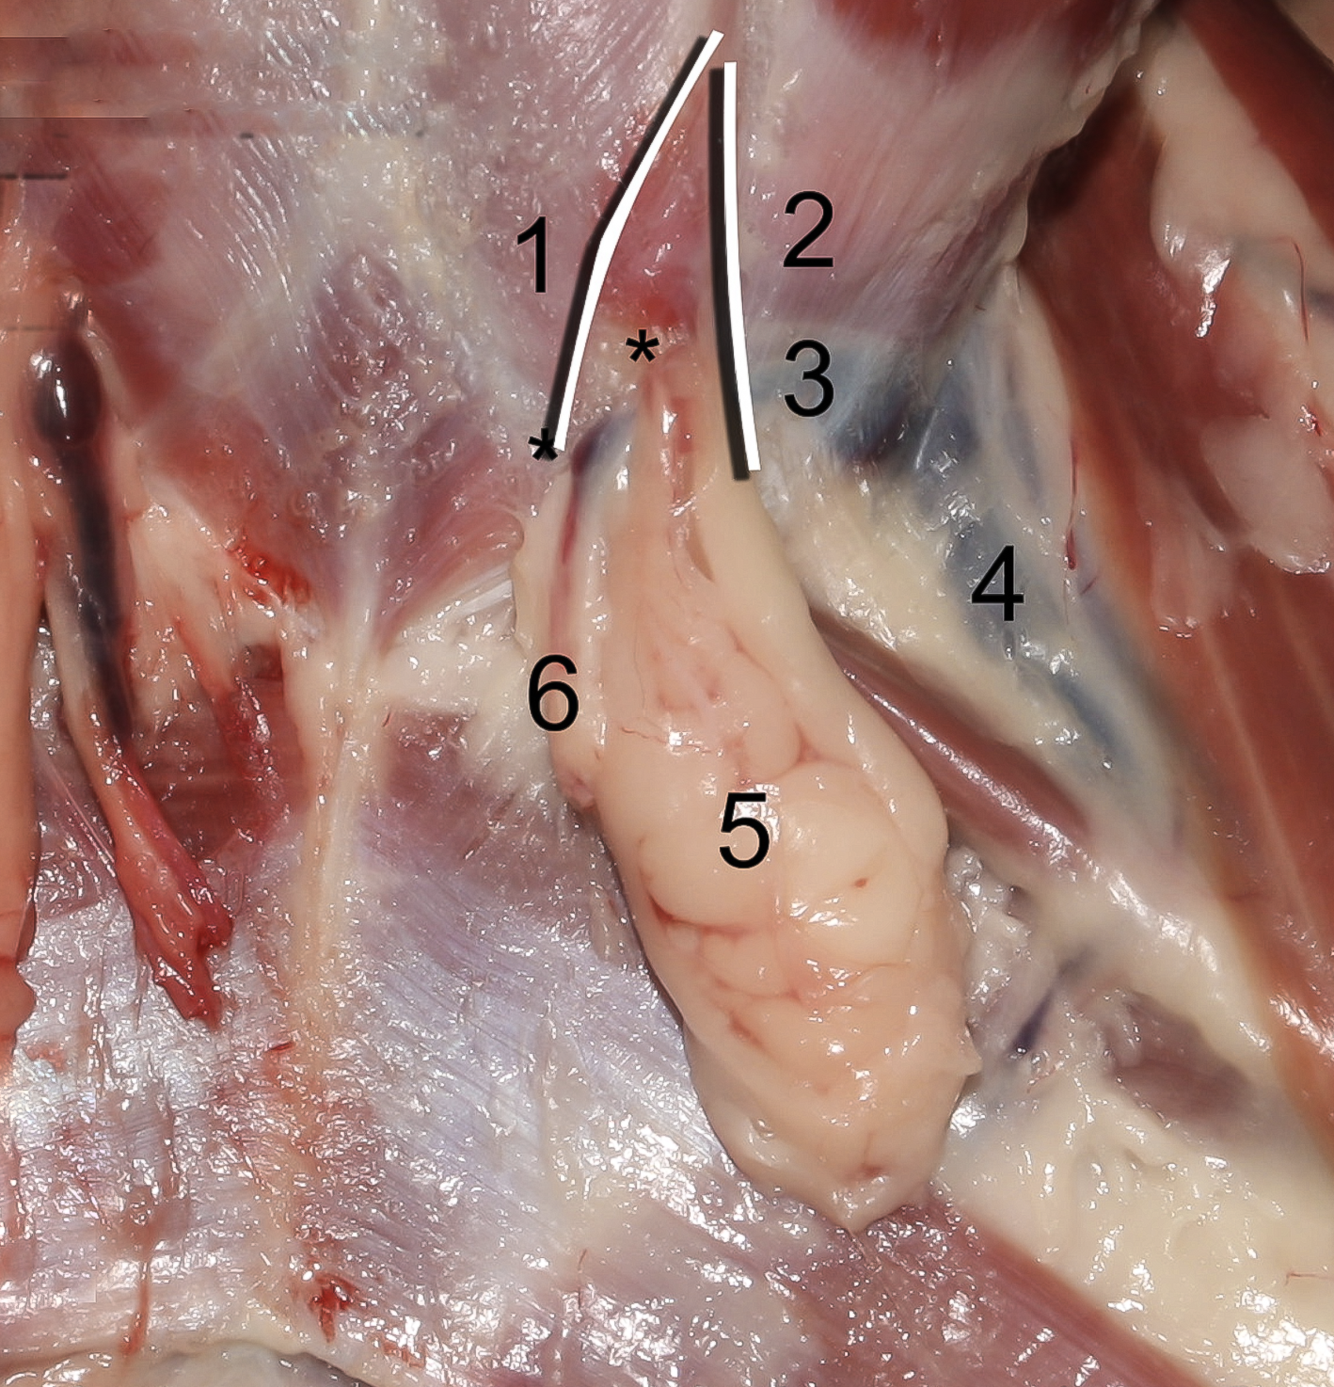

16

Q

Lig. Inguinalis

A

17

Q

3

A

A./v. profunda femoris

- Ex a./v. iliaca externa

- Branches:

- Tr. pudendoepigastrica

- A. epigastrica caudalis

- A. circumflexa femoris medialis

18

Q

4

A

Tr. pudendoepigastrica

- Branches:

- A. pudenda externa

- A. epigastrica caudalis